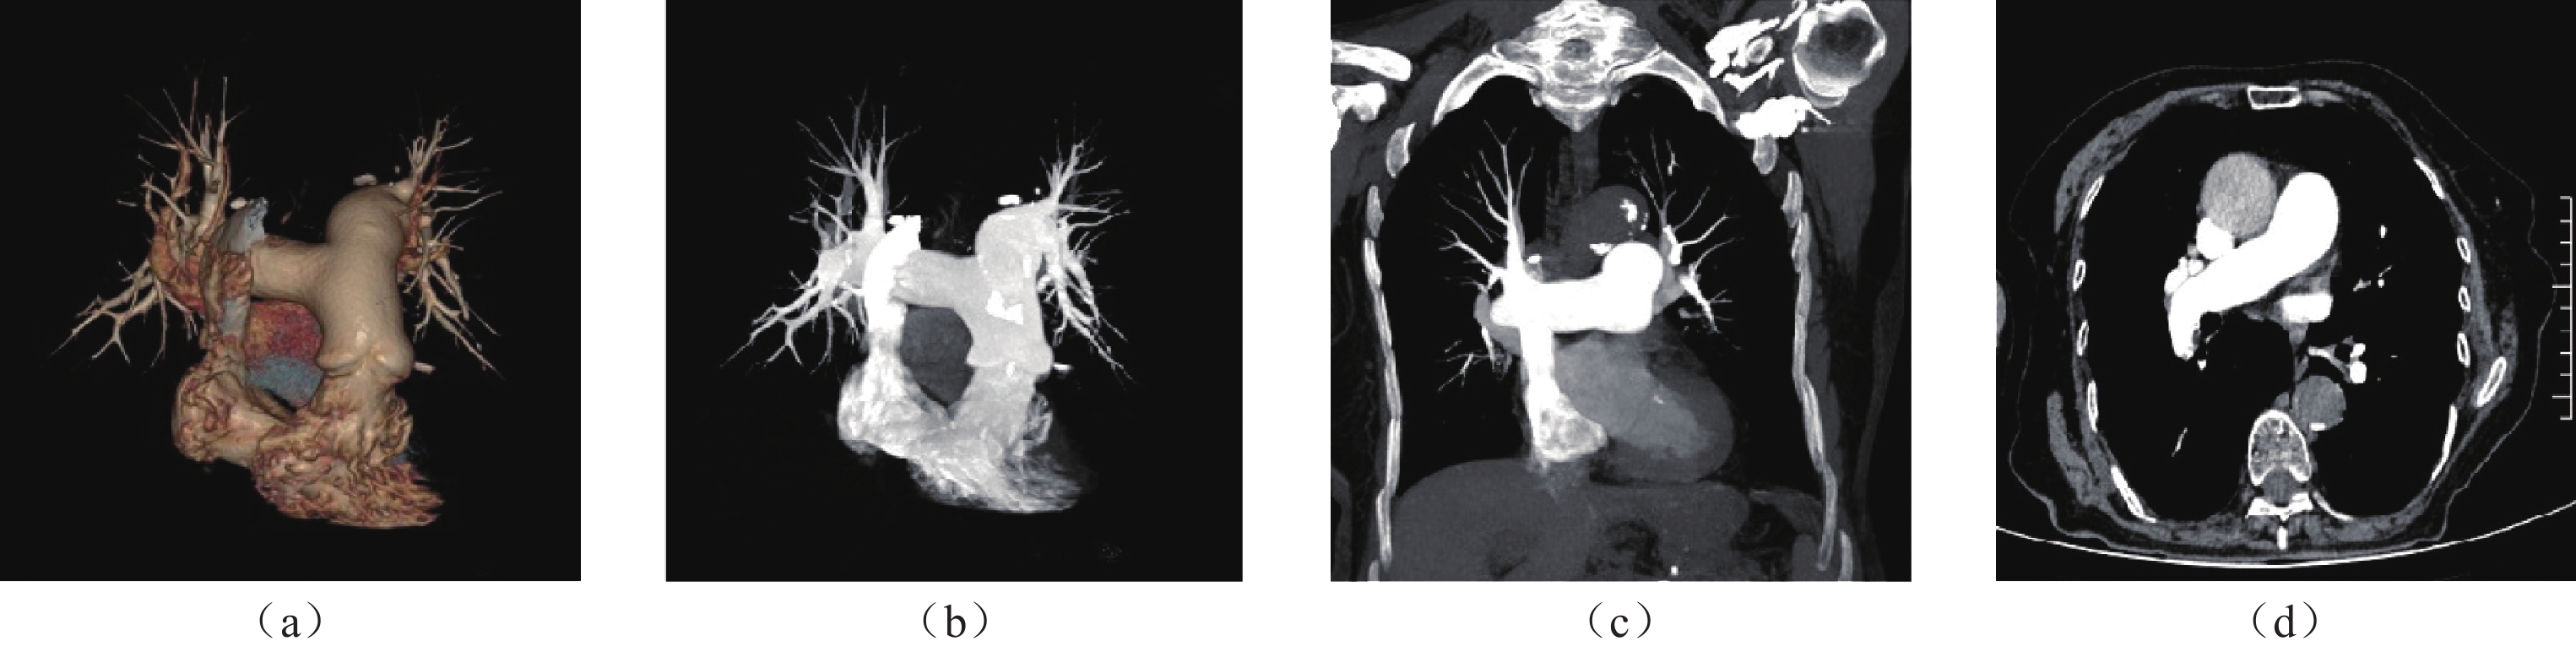

• 摘要: 目的:研究不同时长的个性化对比剂注射方案在提升肺动脉CTA的图像质量和降低对比剂潜在风险的应用价值。资料与方法:2023年1月至2024年10月临床怀疑为肺动脉栓塞的患者106例作为研究对象,随机将患者分配到A、B两组。采用独立样本t检验,比较两组间的上腔静脉的CT值、肺动脉主干的CT值、左肺动脉及右肺动脉的CT值、左房的CT值;两组间的图像质量主观的综合评分;以P < 0.05为具有统计学意义。结果:两组间对比剂注射总量、注射时长和注射速率进行比较,B组对比剂的注射总量和注射时长都低于A组,其差异有统计学意义。两组间的右肺动脉、左肺动脉、左房CT值比较接近,无统计学差异,两组间的上腔静脉CT值差异有统计学差异;两组间的图像质量主观评分比较,有统计学差异,B组>A组。结论:采用8s时长的个性化对比剂注射方案不仅可以提高肺动脉CTA的总体图像质量,还可以有效减少对比剂用量,同时缩短注射时长。

Abstract: Objective: This study investigated the application value of personalized contrast agent injection schemes of different durations in improving the image quality of pulmonary artery CTA and reducing the potential risk associated with contrast agents. Materials and Methods: From January 2023 to October 2024, 106 patients with suspected pulmonary embolism were randomly assigned to Groups A and B. Using the independent samples t-test, we compared the CTA values of the superior venae cavae, pulmonary artery trunks, left and right pulmonary arteries, and left atria of the two groups. We also compared the subjective comprehensive evaluations of the CTA image quality of the two groups; a value of P<0.05 was considered statistically significant. Additionally, the two groups were compared in terms of the total amount of contrast agent injection, injection duration, and injection rate. Both the total amount and duration of contrast agent injection in Group B were lower than those in Group A; the concomitant difference was statistically significant. The CTA values of the right and left pulmonary arteries and the left atria of the two groups were relatively close, with no statistically significant difference. However, a statistically significant difference in the CTA values of the superior venae cavae of the two groups was observed. The subjective evaluation of image quality between the two groups indicated a statistically significant difference (P=0.04), with the image quality of Group B being higher than that of Group A. Conclusion: The use of an 8s personalized contrast agent injection regimen can not only improve the overall image quality of pulmonary artery CTA but also reduce the amount of contrast agent used and shorten the injection duration.